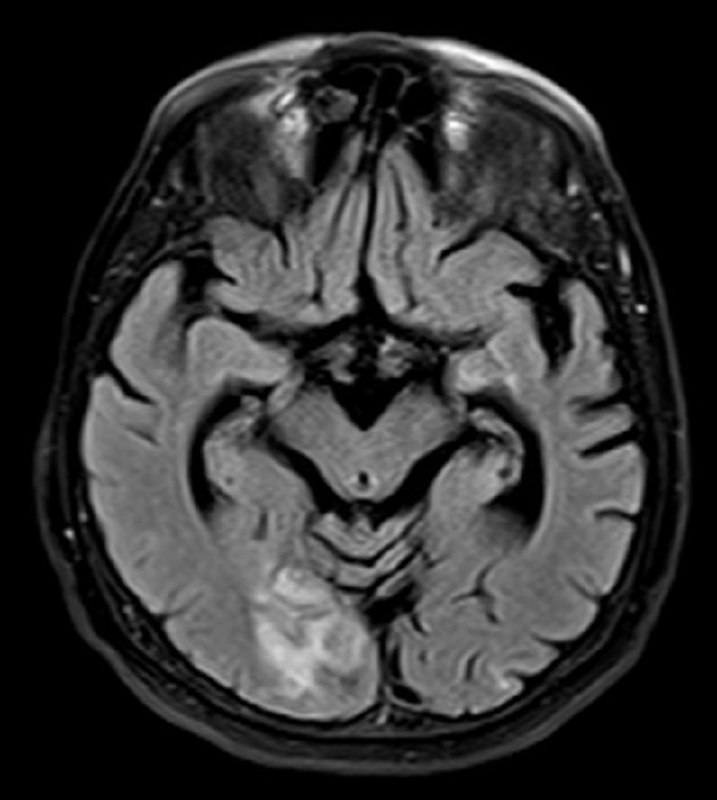

КТ на момент поступления и МРТ при ухудшении состояния через два дня.

Лаборант, по одной, ему лишь ведомой, причине, сделал МРТ фронтальными сканами, пришлось из фронтального сделать аксиальный, для лучшей сравнимости.

Интересно, что ИИ насчитал 9 баллов по ASPECTS, а глазом вообще ничего не видно было.

Тромболитическая терапия не проводилась из-за противопоказаний, через двое суток произошла спонтанная геморрагическая трансформация и инфаркт, как выяснилось, был не 9, а, скорее, 1 балл по ASPECTS.